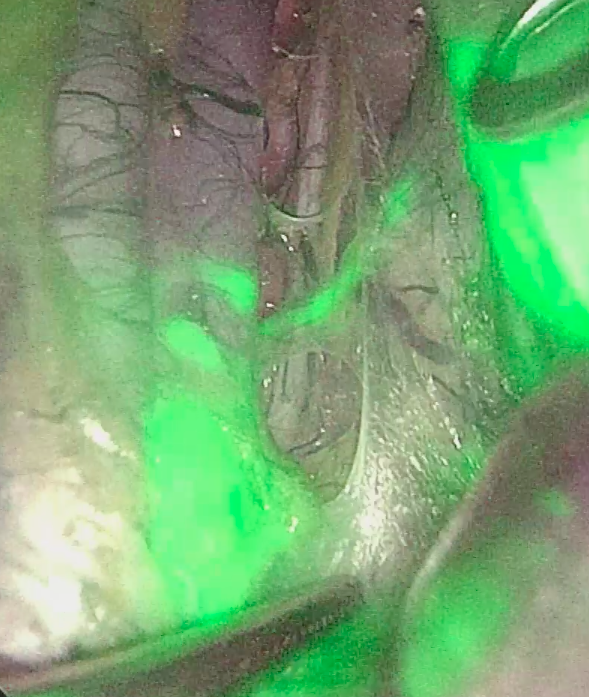

2. Рис. 2. Детекция СЛУ в парааортальных лимфоузлах (лапароскопия). Примечание: рисунок выполнен авторами | |